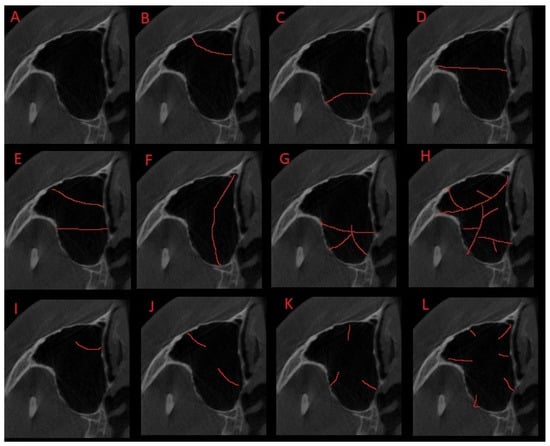

2.3. Methods—Classification Proposal

3.2. Classification Proposal